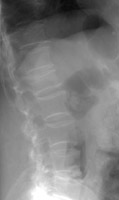

- Click on the image for a larger versionCLateral radiograph of the lumbar spine. This is an image from a different patient and shows a severe compression fracture of the T12 vertebral body.